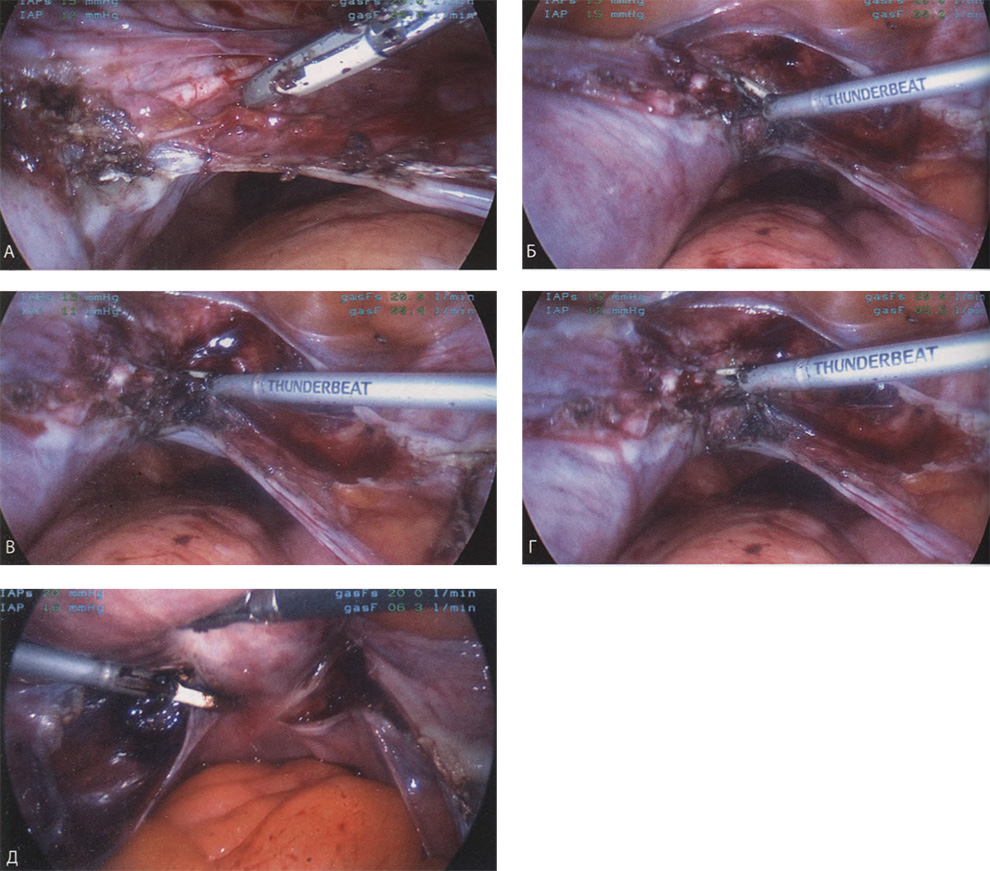

Если оставить в стороне эти достоинства и недостатки, то техника лапароскопической гистерэктомии фактически идентична технике лапаротомической гистерэктомии. В самом начале операции, если она выполняется лапароскопическим методом, необходимо осмотреть всё операционное поле, воспользовавшись для этого панорамным обзором (рис. 12-33—12-37). Операцию начинают с коагуляции и пересечения круглых связок, чем обеспечивается доступ к широкой связке (рис. 12-38—12-40). Брюшину, переходящую с купола мочевого пузыря на переднюю поверхность матки, вскрывают. Пузырь отсепаровывают от матки острым путём (рис. 12-41). После этого вскрывают задний листок широкой связки, а затем принимают решение, оставлять или удалять яичники. Если принято решение оставить яичники, то коагулируют и пересекают собственные связки яичников и маточные трубы (рис. 12-42). Если принято решение удалить яичники (то есть выполнить сальпингоофорэктомию), то с обеих сторон выполняют диссекцию мочеточников от воронко-тазовых связок, которые затем отсепаровывают, коагулируют и пересекают (рис. 12-43). Затем ткань широкой связки отделяют от маточных сосудов (отпрепаровывая их), изолировав, таким образом, мочеточники от маточных сосудов (рис. 12-44 А). Восходящие ветви маточных сосудов коагулируют справа и слева, а затем пересекают (рис. 12-44 Б, В).

Коагулируют и пересекают так называемые поддерживающие связки матки (рис. 12-44 Г, Д). Возможно, потребуется разделить ткани, соединяющие мочевой пузырь с передней стенкой влагалища. После этого вскрывают влагалище и коагулируют все кровоточащие сосуды. Если хирург владеет методами лапароскопического наложения швов, то он зашивает культю влагалища. Предварительно матку извлекают через влагалище или путём морцелляции (рис. 12-45 и 12-46).

Рис. 12-44. А. Маточные сосуды выделены на протяжении, коагулированы и пересечены. Б. Увеличенное изображение пересечённой кардинальной связки. В. Отсечена соединительная ткань, поддерживающая шейку ха. Г. Увеличенное изображение В. Д. Коагулирована и пересечена крестцово-маточная связка.